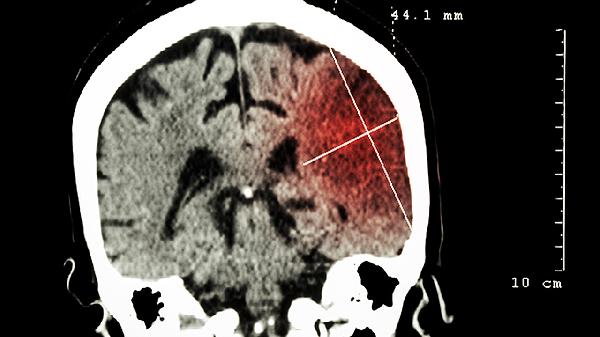

脑脓肿有什么症状和治疗方法

脑脓肿的症状主要包括头痛、发热、神经系统功能障碍等,治疗方法有抗生素治疗、手术引流等。脑脓肿通常由细菌感染、真菌感染、中耳炎扩散、鼻窦炎扩散、外伤感染等原因引起,可通过药物治疗、手术治疗、对症支持治疗